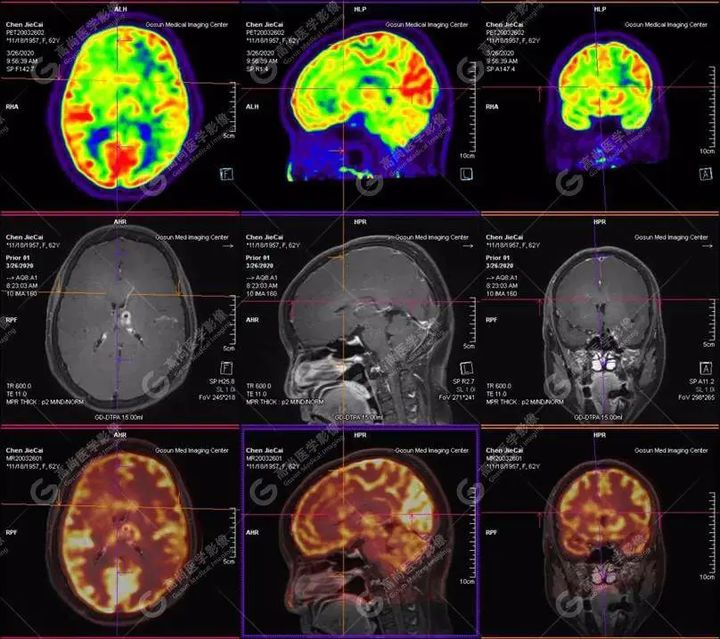

【高尚醫(yī)療影像】【多模態(tài)影像】顱內(nèi)淋巴瘤PET-MR融合顯像1例

【病史摘要】患者,女,62歲

失眠伴記憶力減退近一月入院檢查,無(wú)頭痛、嘔吐、四肢活動(dòng)正常

外院CT提示,顱內(nèi)多發(fā)占位,轉(zhuǎn)移瘤可能

影像圖

【PET-MR融合診斷】

左側(cè)顳葉、頂葉、左側(cè)基底節(jié)區(qū)及胼胝體部多發(fā)結(jié)節(jié)狀高代謝病灶,部分合并囊變、出血,MR平掃+增強(qiáng)示不均勻輕、中度強(qiáng)化,綜合考慮為顱內(nèi)原發(fā)惡性腫瘤,以淋巴瘤可能性大

【病理結(jié)果】彌漫大B細(xì)胞淋巴瘤